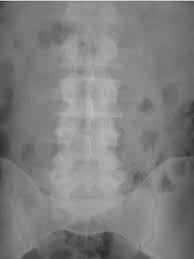

What Size Kidney Stones Show Up On Xray. Kidney stones of less than 5mm are considered to be small. You are interested in.

Ivan ip answered 12 years experience hospital based practice. In addition results may show the presence of kidney stones or gallstones. Node etc show up on plain xray and ct low back pn clear l spine xray and ct to look for kidney stones etc.